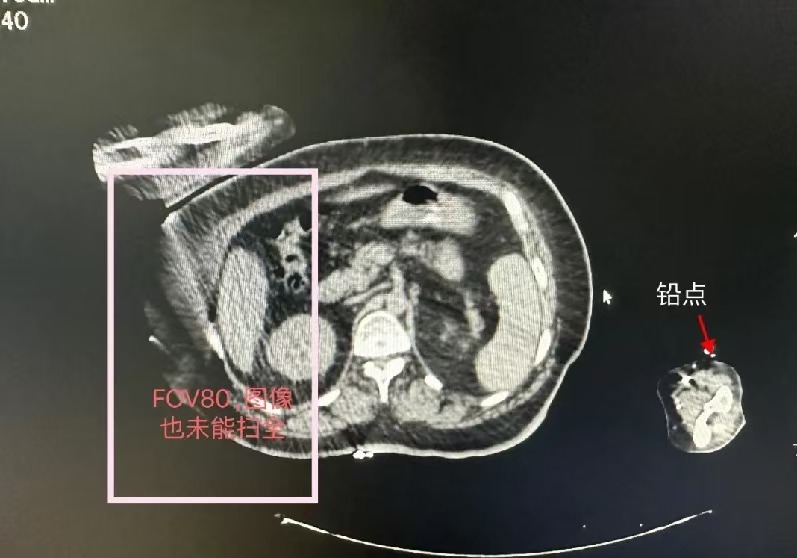

这位患者的定位有三大难点,一是要保证患者手臂远离身体,在治疗肿瘤的过程中尽量减少正常组织照射剂量;二是不能偏床太多,要保证在加速器室治疗时能正常旋转机架,不中断其出束;三是患者体形微胖,要选择常规定位胳膊置于体侧且不影响其扣膜。

为了克服这三个难点,科室人员结合患者实际情况,多次论证,进行了充分的讨论研究与实践测试。先后排除了乳腺托架、真空垫以及常规定位扣膜等方式。

基本上能使用的常规与非常规方式均已尝试,依然没能完美解决。但是整个放疗定位团队没有放弃,而是拓宽思路、集思广益,提议将其手臂上举,使用颈胸膜的上半部分将其手臂固定在头托位置,但不放置头托,这次效果非常理想。经过大家的不懈努力,终于为患者在放疗模拟机定位时找到的最合适、重合度最高的固定体位,为其后续进行放射治疗奠定了非常好的基础。